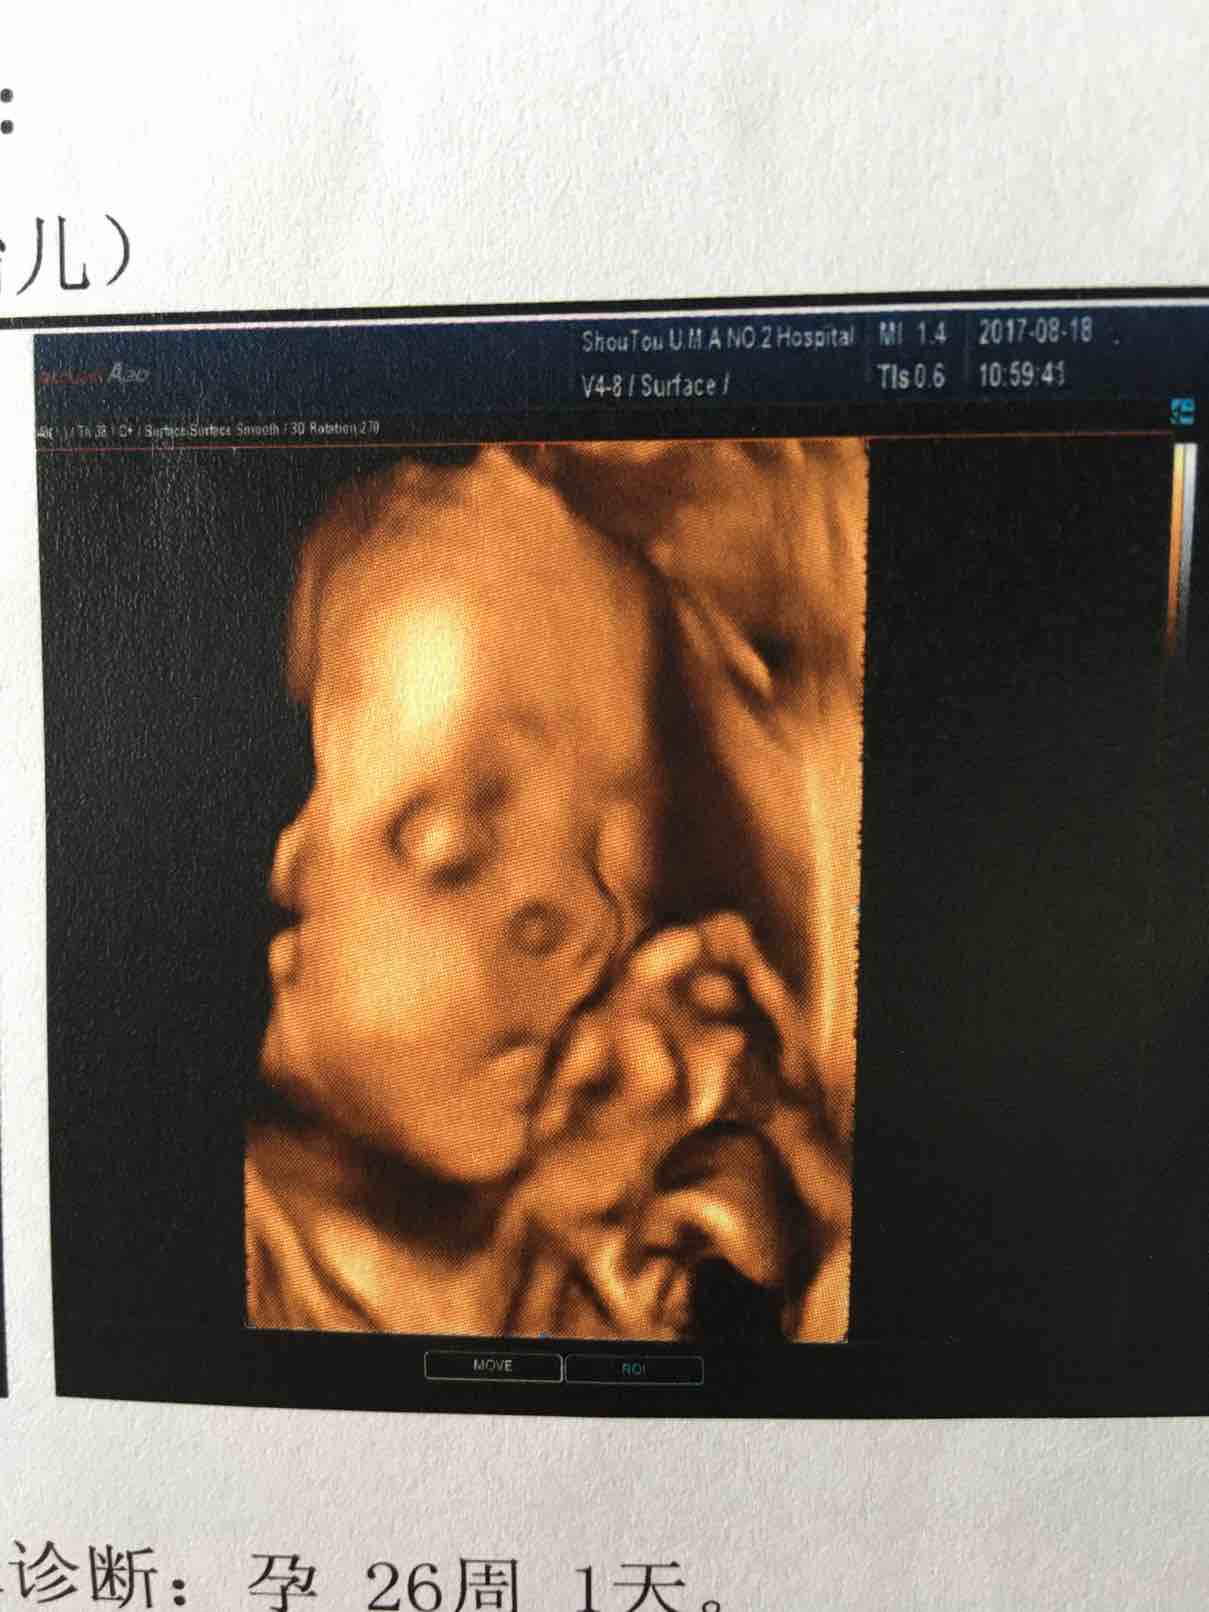

四维彩超

终于做了四维,很开心跟宝宝见面,可是查完医生说肾盂分离,数值不大,医生让一个月后复查看会不会宝宝自己吸收,好担心,在网上查了说不超过10mm就没事,有可能宝宝自己调皮憋尿,接下来这个月怎么过啊

好可爱的宝宝啊,9月2号我也要去做系统b超,好像也是四维吗,希望也能看看我的宝宝。

看上去就像男孩,肯定是的,呵呵